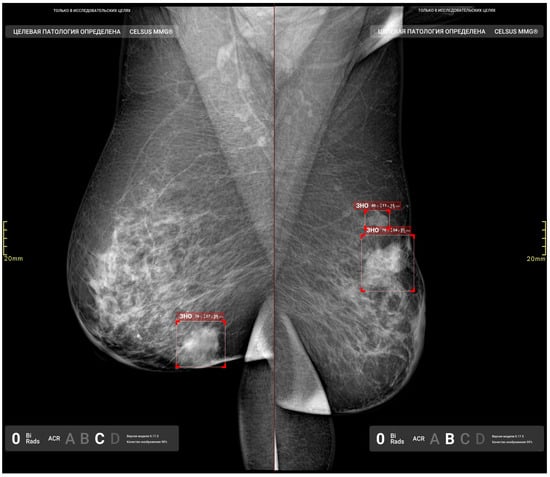

2.2. AI Solution Overview

| 1 | Detection, segmentation, and classification (benign/malignant) of masses | Graphical mask, text | DICOM, DICOM SR, Apache Kafka message |

| 2 | Detection, segmentation, and classification (benign/malignant) of calcifications | ||

| 3 | Detection and segmentation of enlarged lymph nodes | ||